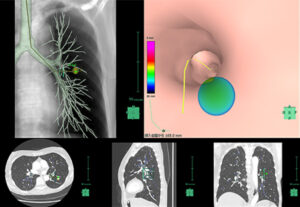

关于支气管镜检查,也正下工夫,正检查400件左右例年。针对肺癌的诊断,正为出自假定支气管镜图片的导航仪以及超声波内窥镜,出自小路支气管镜的活用的诊断率的提高努力。另外,也和放射照射疗法科合作,正进行供对肺的照射使用的金属万能笔拘留根据合适对需要放射照射疗法的患者也。